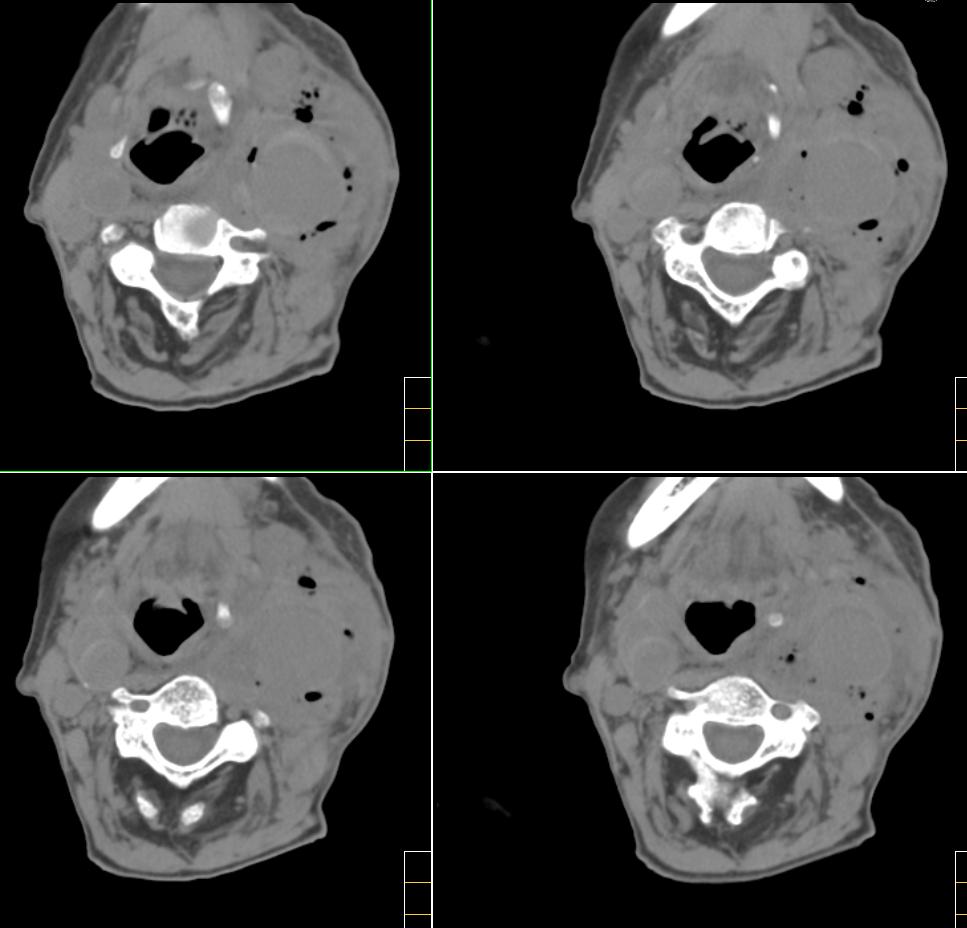

标题: CT4272:求助!颈部血管瘤破裂?

f、72y,左侧颈部发现包块及疼痛1周,彩超提示颈部血管破裂?

除上诉考虑外,那么多而且不规则、不定形的钙化还应该想到有颈部畸胎瘤的可能性。顺着思路继续,颈部畸胎瘤继发产气菌感染,并在颈总动脉局部形成小脓肿且浸蚀到血管壁。

左颈部血管增粗,周围软组织肿胀模糊,内有蜂窝状积气影,左侧甲状腺增大,气管受压右移,气管软骨环未受侵。结合病史较短考虑:左颈部脓肿破裂并血管瘤形成,左甲状腺瘤。

考虑左侧甲状腺癌破坏气管,并颈部积气、淋巴结肿大。